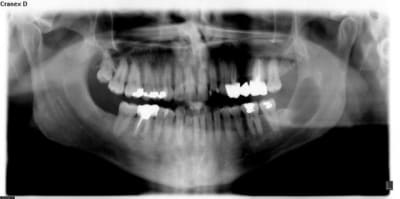

Un autre kyste mais dans l'angle cette fois-ci.

Le plus dur a été de disséqué le lingual car la corticale était rompue ! Heureusement le patient n'a eu aucune séquelle.